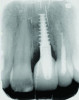

Patient 2: A 63-year-old healthy male patient presented with implant No. 6 exhibiting RPI, having been affected by previously endodontically treated and fractured tooth No. 5 (Figure 3 and Figure 4). The implant had probing depths ranging from 4 mm to 10 mm (Table 1) with the most severe bone loss at the distal aspect of implant No. 6 (Figure 3 and Figure 4).

Fig 3 and Fig 4. Case 2: Initial clinical presentation showing implant No. 6 with RPI, having been impacted by fractured tooth No. 5 (Fig 3); radiograph showing fractured tooth No. 5 with periapical lesion extending to the distal aspect of implant No. 6 (Fig 4).

Figure 3

Fig 4. Case 2: Initial clinical presentation showing implant No. 6 with RPI, having been impacted by fractured tooth No. 5 (Fig 3); radiograph showing fractured tooth No. 5 with periapical lesion extending to the distal aspect of implant No. 6 (Fig 4).

Figure 4